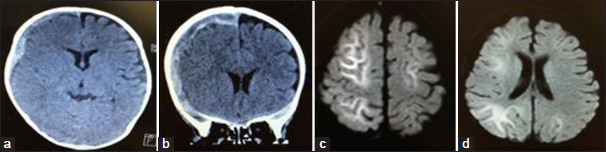

背景:具有两期临床病程和晚期弥散减弱(TBIRD)的婴儿创伤性脑损伤是一种类似于急性脑病的两期癫痫发作和晚期弥散减弱,其特征是明亮的树状外观和潜在的后遗症。虽然癫痫在儿童创伤性脑损伤(TBI)中很常见,但将TBIRD与其他癫痫病因区分开来是至关重要的。本研究比较了创伤性脑损伤(TBI)患者的临床特征,包括有和没有癫痫发作的患者,确定了TBIRD病例,并检查了他们的特征。方法:对2016年3月至2023年7月儿科重症监护病房收治的创伤性脑损伤(TBI)患儿数据进行分析。患者分为癫痫和非癫痫两组。比较临床特征,并在癫痫组中确定TBIRD病例进行分析。结果:104例患者中28例发生癫痫发作,76例未发生癫痫发作。癫痫发作组明显年轻化,硬膜下血肿(SDHs)患病率较高,且与癫痫发作密切相关(dds比OR = 6.73, 95%: 1.99 ~ 22.8, P = 0.00216)。在28例癫痫患者中,5例被诊断为TBIRD,所有患者均表现为SDH和癫痫持续状态。非SDH患者无TBIRD。癫痫持续状态在TBIRD病例中比在非TBIRD病例中更为常见。结论:本研究提示癫痫发作是TBIRD的一个标志,与硬膜下血肿(SDH)密切相关。所有TBIRD病例均涉及SDH和癫痫持续状态,而未发生SDH的TBIRD病例均未发生。伴有SDH和癫痫持续状态的TBI患者需要谨慎管理,因为有发展为TBIRD的风险。

Background: Infantile traumatic brain injury with a biphasic clinical course and late reduced diffusion (TBIRD) is a condition resembling acute encephalopathy with biphasic seizures and late reduced diffusion, marked by a bright tree appearance and potential sequelae. Although seizures are common in pediatric traumatic brain injury (TBI), distinguishing TBIRD from other seizure etiologies is crucial. This study compared the clinical characteristics of patients with traumatic brain injury (TBI), including those with and without seizures, identified TBIRD cases, and examined their distinguishing features.